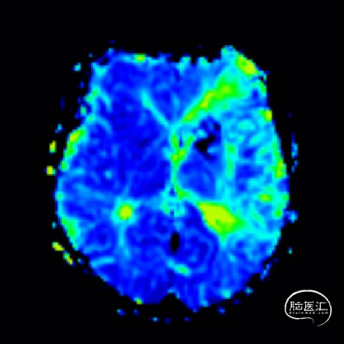

术后即刻影像。

支架植入后造影提示残余狭窄约10%。术中患者生命体征稳定,术后患者恢复良好出院,继续抗血小板聚集及他汀类药物治疗。